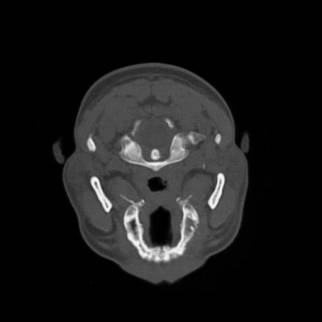

Figura 1‑2 Immagine TAC relativa ad una sezione trasversale del cranio.